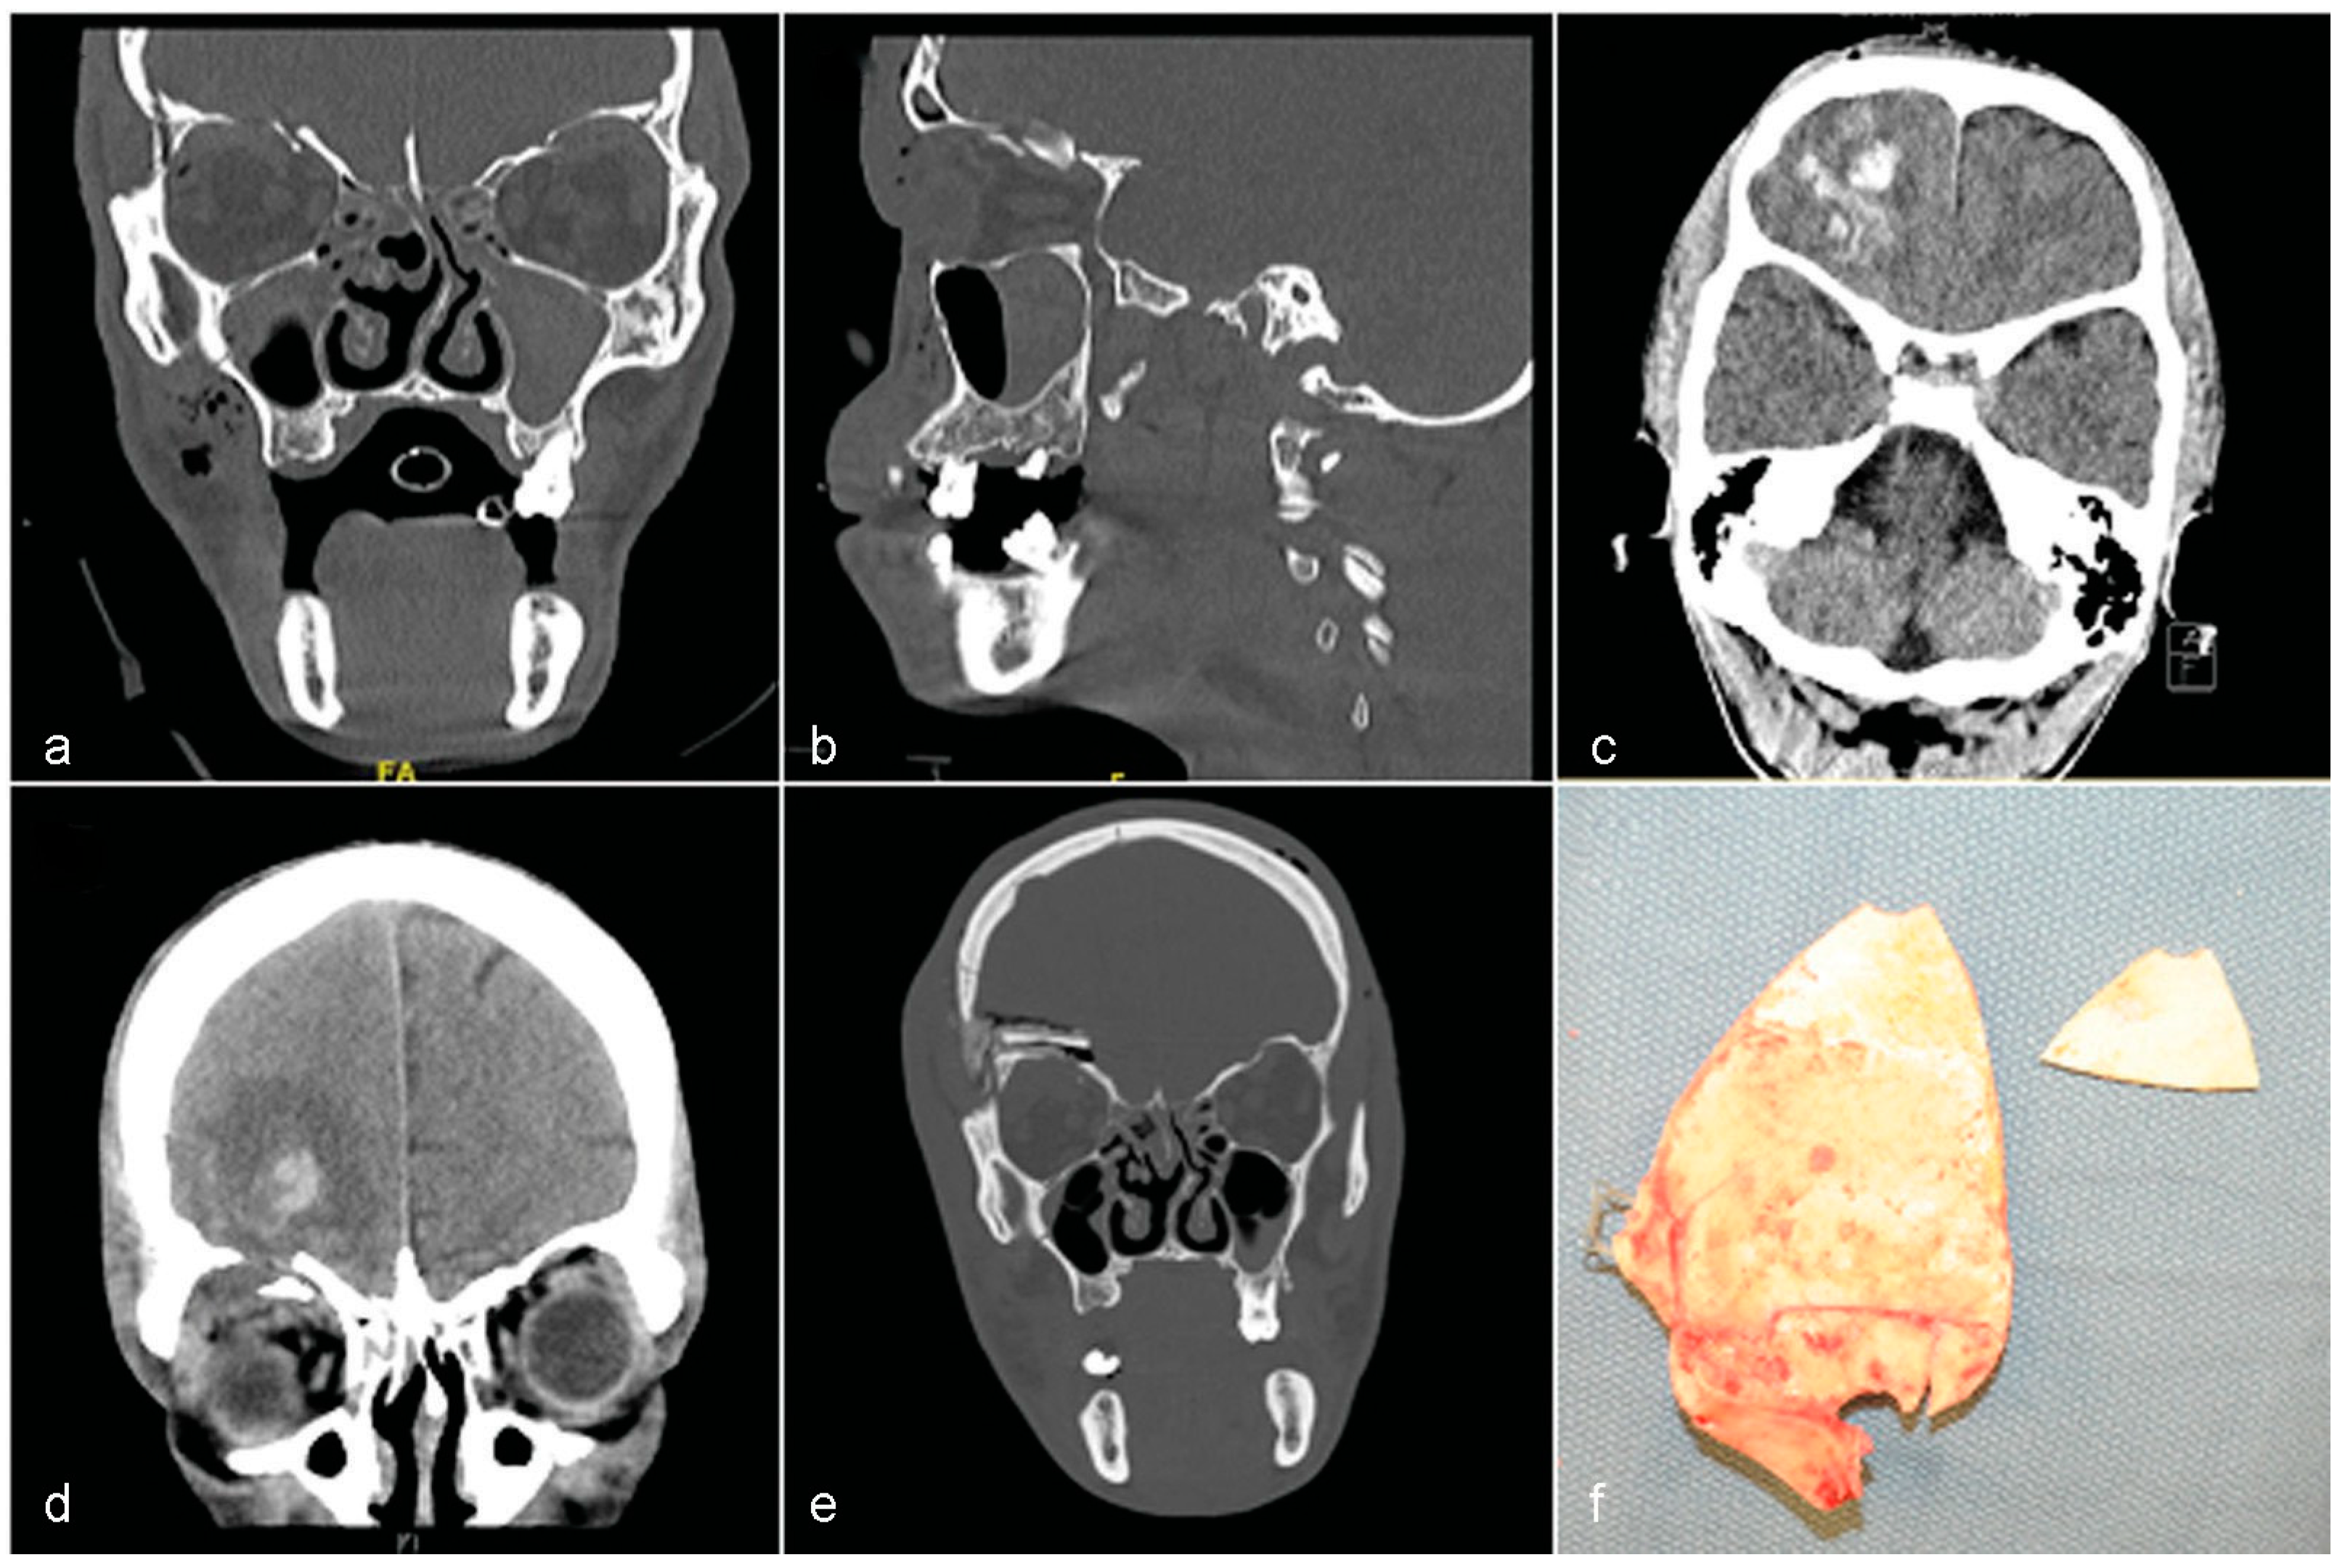

Case 2